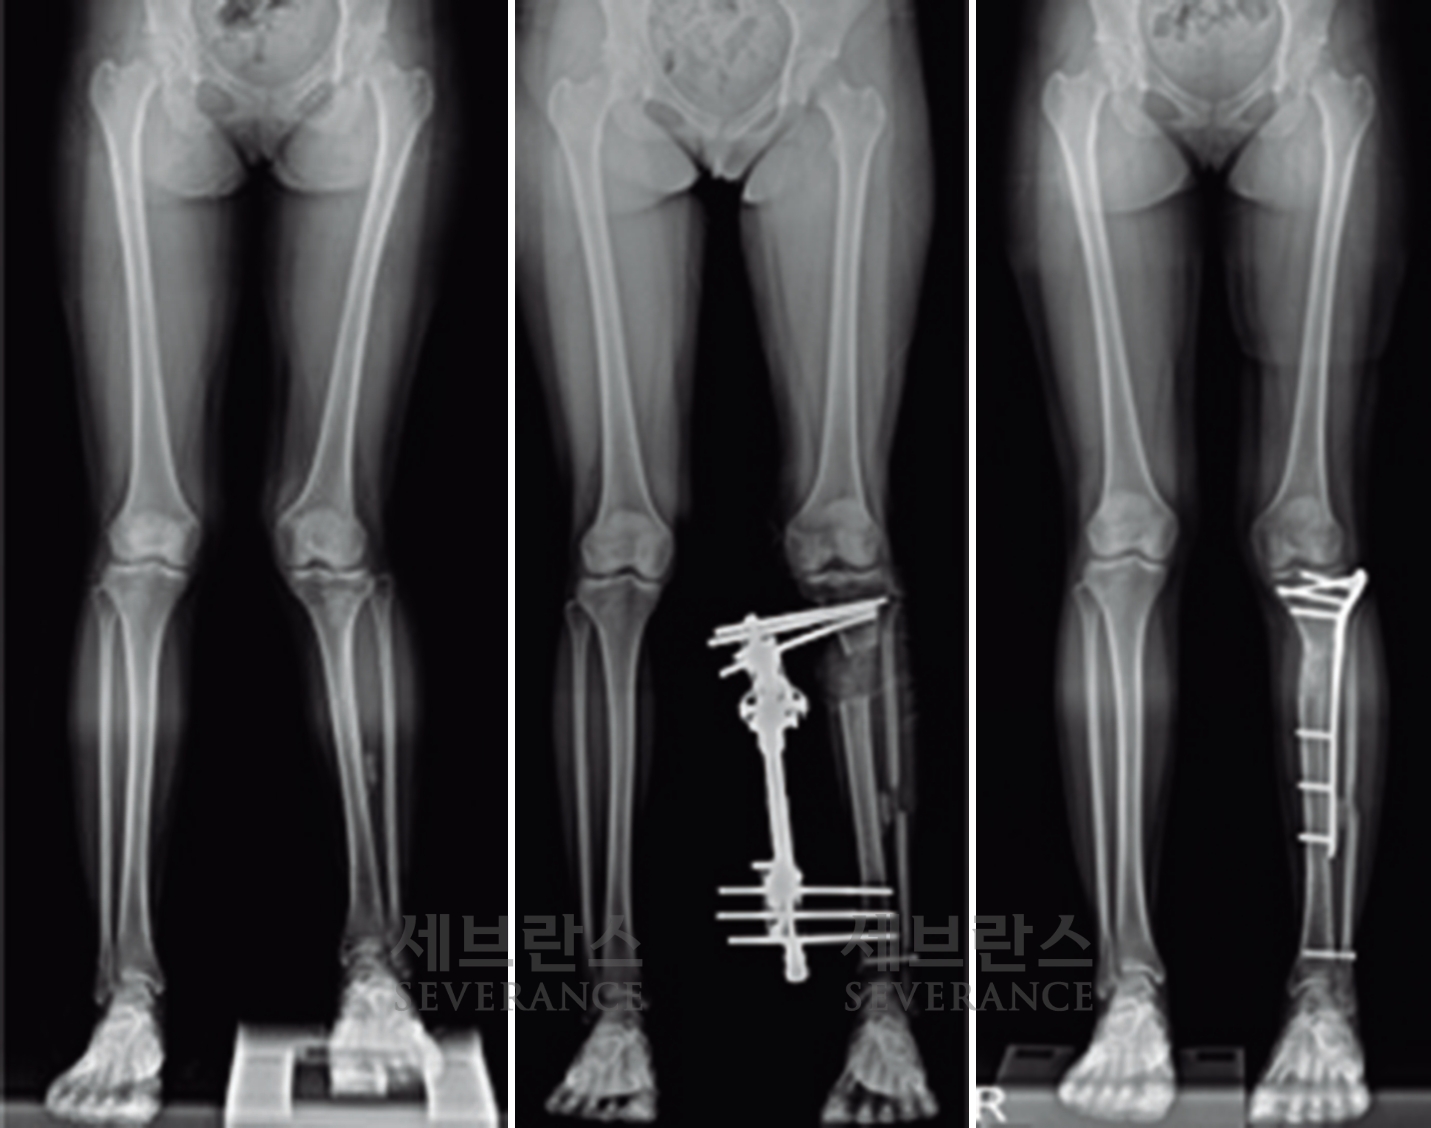

성장판 손상으로 발생한 좌측 외반슬 및 하지부동에 대해 골연장술과 교정술을 동시에 시행해 치료한 환아

양쪽 팔다리의 길이 차이가 큰 경우에 주로 시행하는 수술로, 외부 고정 장치나 내부 금속정을 이용해 뼈를 서서히 늘려 균형을 맞추는 방법입니다. 대체로 외부 고정 장치를 많이 사용하는데, 연장 기간 동안 날마다 정해진 횟수만큼 뼈를 조금씩 늘려야 하고, 핀 주변 소독도 꾸준히 해줘야 합니다. 연장된 뼈가 단단히 붙는 데도 수개월이 걸리기 때문에 환자와 보호자의 인내가 필요합니다.